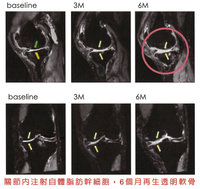

運動表現下滑膝蓋痛 自體脂肪幹細胞助免換人工關節

2025/05/06 12:54

#阿傑

#衛福部

#雙北市

社會